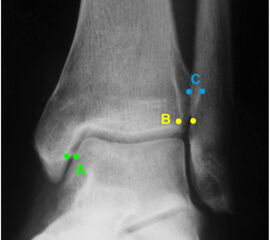

Die Standard-Röntgenaufnahmen des oberen Sprunggelenks bestehen aus drei Aufnahmen: der antero-posterioren Aufnahme (ap), der antero-posterioren Aufnahme mit Innenrotation des Unterschenkels von 20° („Mortise view“), sowie der streng seitlichen Aufnahme (siehe S2-Leitlinie Sprunggelenksfraktur). In der Röntgen-Bildgebung sollte neben den klassischen Frakturzeichen die Integrität der Syndesmose beurteilt werden. Dies erfolgt über die Beurteilung der Breite des lateralen und medialen Gelenkspalts („medial clear space“), des tibiofibularen Abstands 1cm oberhalb des OSG-Gelenkspalts („tibiofibular clear space“), bzw. der tibiofibularen Überlappung. Eine Verbreiterung des tibiofibularen Abstands über 5 mm oder die Erweiterung des medialen Gelenkspalts können Zeichen einer begleitenden Syndesmosenverletzung sein. (Abbildung 3) 6.